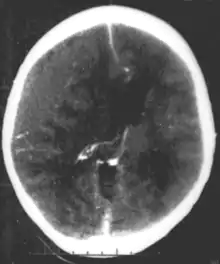

| Epidural hematoma, an example of a focal injury |

- Epidural hemorrhage is bleeding between the dura mater and the skull.[4] It is commonly associated with damage to the middle meningeal artery, often resulting from a skull fracture.